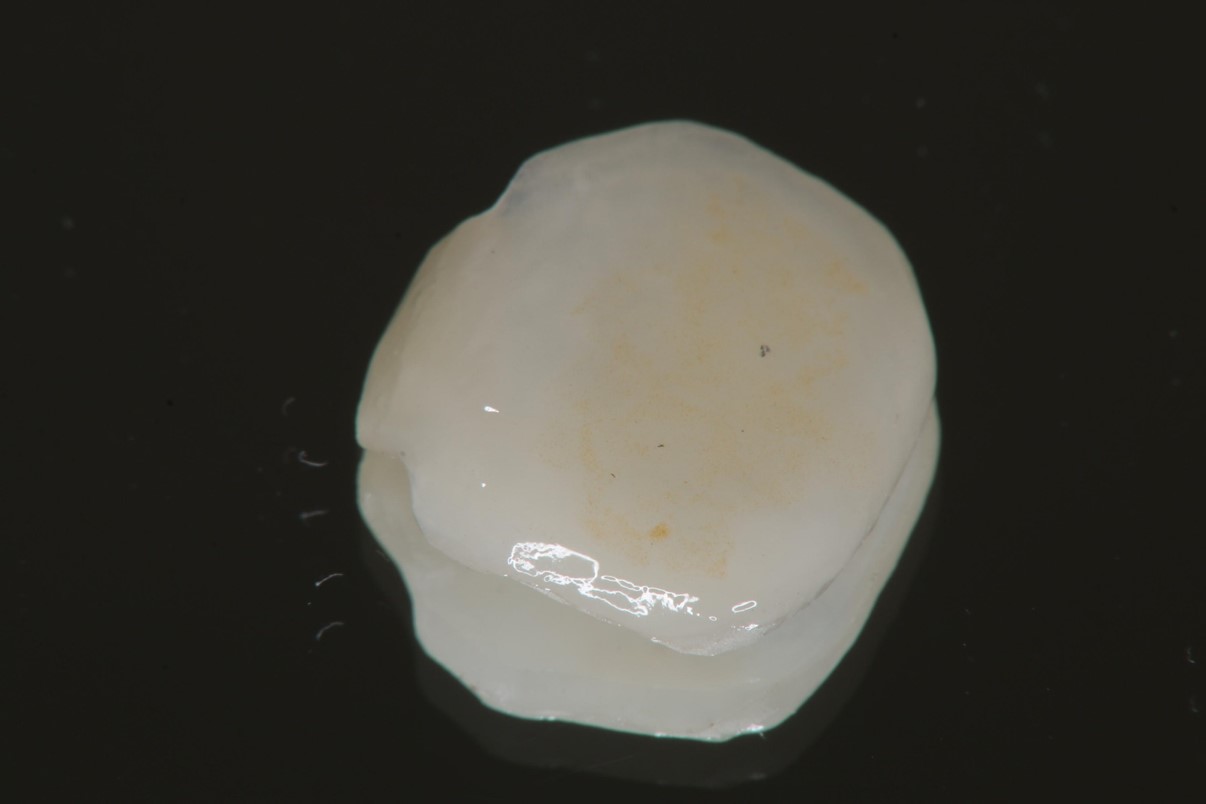

陶瓷冠塊體製作

陶瓷冠塊體